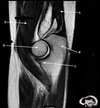

1

Q

What is letter A?

SUPRASPINATUS TENDON

2

What is letter B?

A

ACROMION